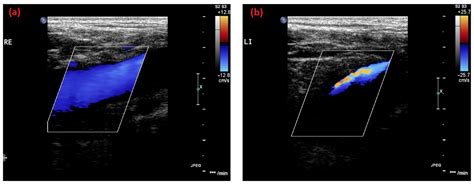

May-Thurner Syndrome, also known as iliac vein compression syndrome, occurs when the left common iliac vein is compressed by the right common iliac artery against the spine. This compression creates a mechanical obstruction that slows down blood flow from the left leg back toward the heart. When blood flow is restricted, the blood is more likely to pool and clot, a condition known as Deep Vein Thrombosis (DVT). If left untreated, these clots can potentially break loose and travel to the lungs, resulting in a pulmonary embolism, which is why early detection is critical.

One of the most important factors in maintaining a normal Maythurner Syndrome life expectancy is regular monitoring by a vascular surgeon or interventional radiologist. Periodic ultrasound imaging (Duplex scans) allows doctors to ensure that the stent remains patent—meaning it is open and functioning correctly—and that there is no narrowing or obstruction developing within or around the stented area. Through proactive follow-up, any minor issues can be addressed before they escalate into serious health concerns.